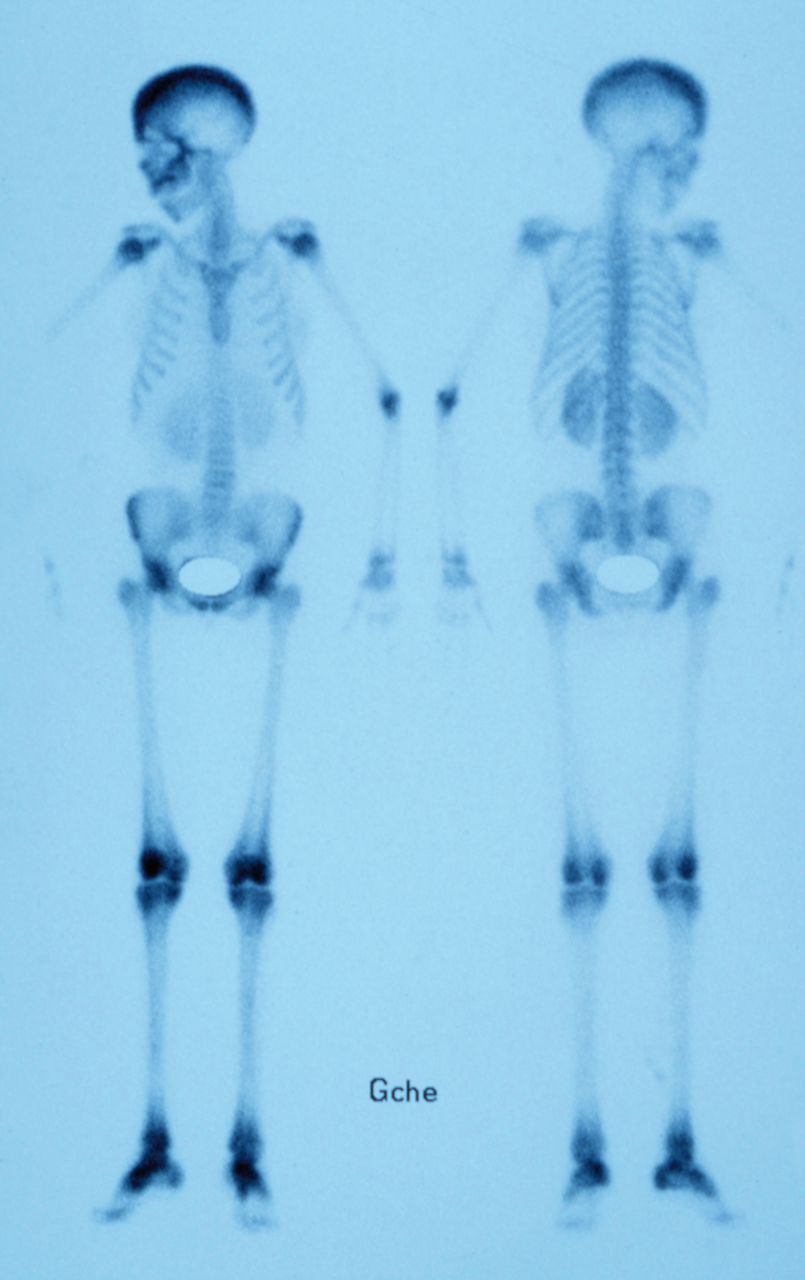

Quel est votre diagnostic ? Maladie de Paget Métastases cérébrales Plasmocytome Bêta-thalassémie Il s'agit d'une bêta-thalassémie. Pour en savoir plus :- Thuret I. Prise en charge des bêta-thalassémies. Rev Prat 2014;64(8):1132-7. - Dossier "Maladies de l'hémoglobine". Rev Prat 2014;64(8):1107-39. Histiocytose OK Valider mes réponses